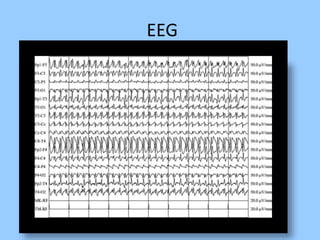

1. The document discusses EEG patterns and findings in various neurological conditions seen in children. It includes descriptions of normal EEG findings as well as abnormal patterns seen in conditions like absence seizures, West syndrome, benign childhood epilepsy with centrotemporal spikes, Lennox-Gastaut syndrome, non-convulsive status epilepticus, subacute sclerosing panencephalitis, and herpes encephalitis.

3. International standards for EEG electrode placement and recording parameters are reviewed. Characteristics of different EEG waves, amplitudes, and patterns are described.